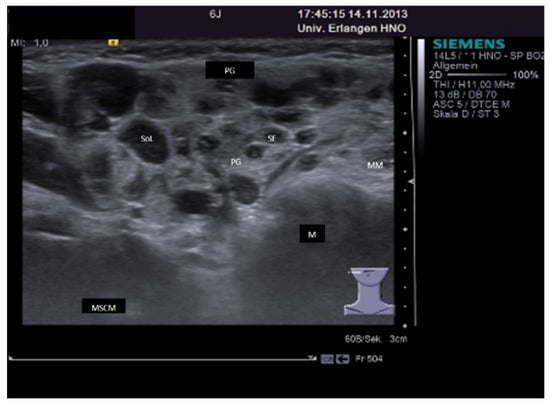

3.4.3. Sjoegren’s Syndrome/Disease

3.4.4. IgG4-Associated Involvement of Salivary Glands